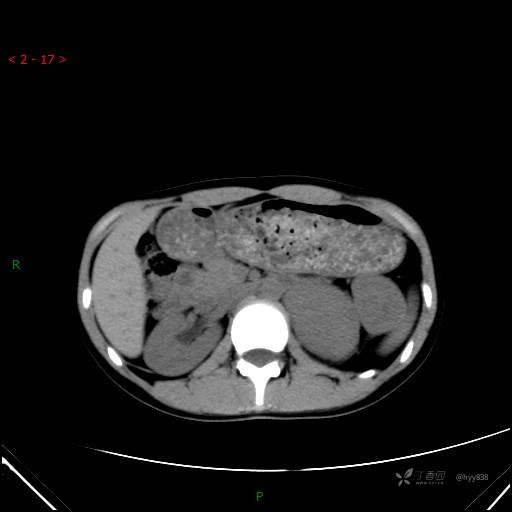

增强动脉期